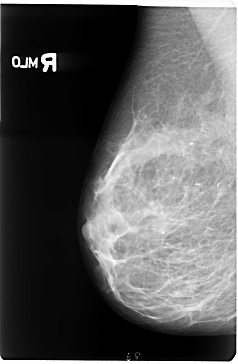

B_3047_1.LEFT_MLO

LEFT_MLO LINES 4704 PIXELS_PER_LINE 3112 BITS_PER_PIXEL 12 RESOLUTION 50 OVERLAY